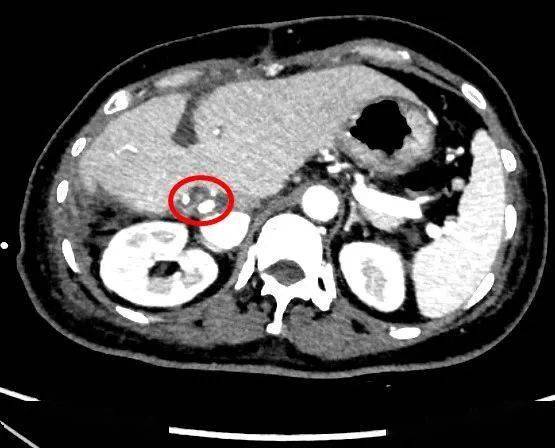

b超和ct检查显示他的胆管内有明显扩张,胆囊壁增厚,肝内胆管也有扩张